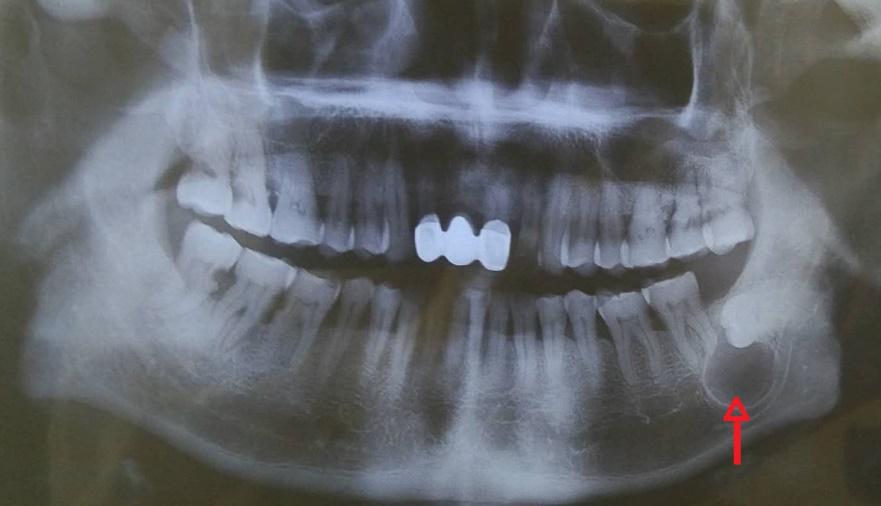

牙痛的发生一般是因为牙本质受到了损害,如果不及时进行治疗的话,后期容易影响到牙髓,产生炎症,如根尖炎,长期不处理的话在炎症的反复刺激下,就容易慢慢形成囊肿。

出现囊肿怎么办?

如果囊肿比较小,可以先观察情况,如果会渐渐变小就不用理会,但是患牙必须要及时进行治疗。如果囊肿比较大,就要及时进行手术治疗,要不然容易波及其他健康的牙齿并造成骨头被吸收越来越多。